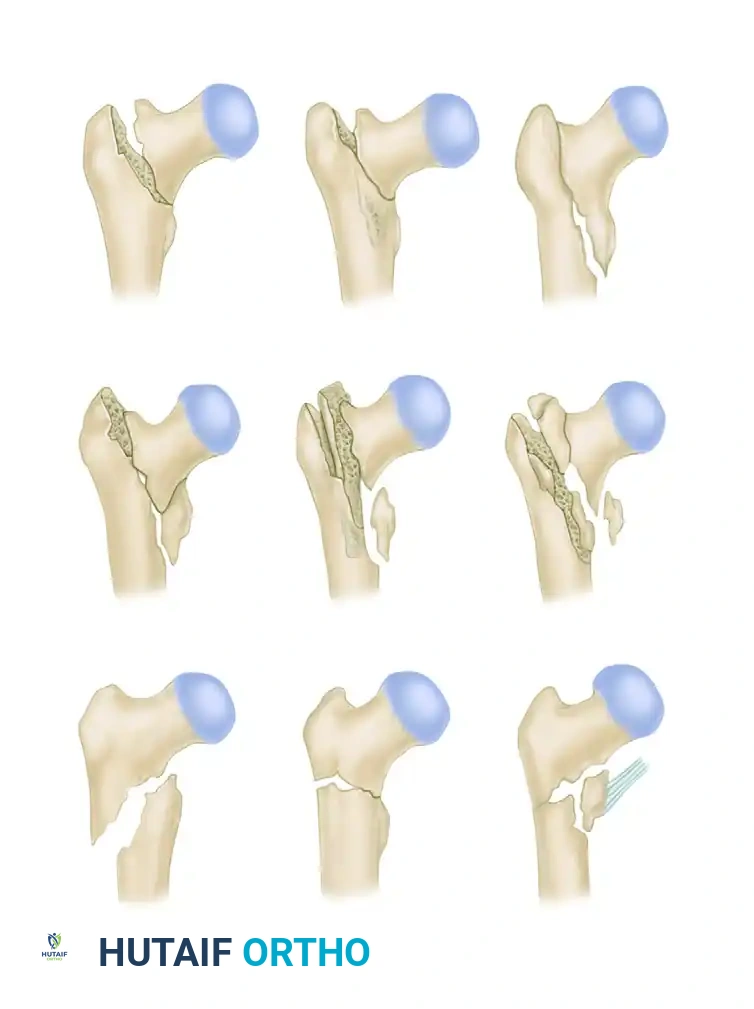

The AO/OTA Classification

The Comprehensive Classification of Fractures (AO/OTA) divides trochanteric fractures (31-A) into three primary groups:

* 31-A1: Simple, two-part fractures with a stable medial cortex.

* 31-A2: Multifragmentary fractures with posteromedial comminution (incompetent medial buttress) but an intact lateral wall.

* 31-A3: Reverse obliquity or transverse fractures extending through the lateral cortex.

Boyd and Griffin Classification

An alternative historical framework is the Boyd and Griffin classification, which highlights the complexity and potential for instability in trochanteric fractures.

While A1 and stable A2.1 fractures are highly amenable to CHS fixation, fractures with significant lateral wall comminution (A2.2, A2.3, and A3) exhibit a high failure rate with side-plate devices due to excessive medialization of the femoral shaft.